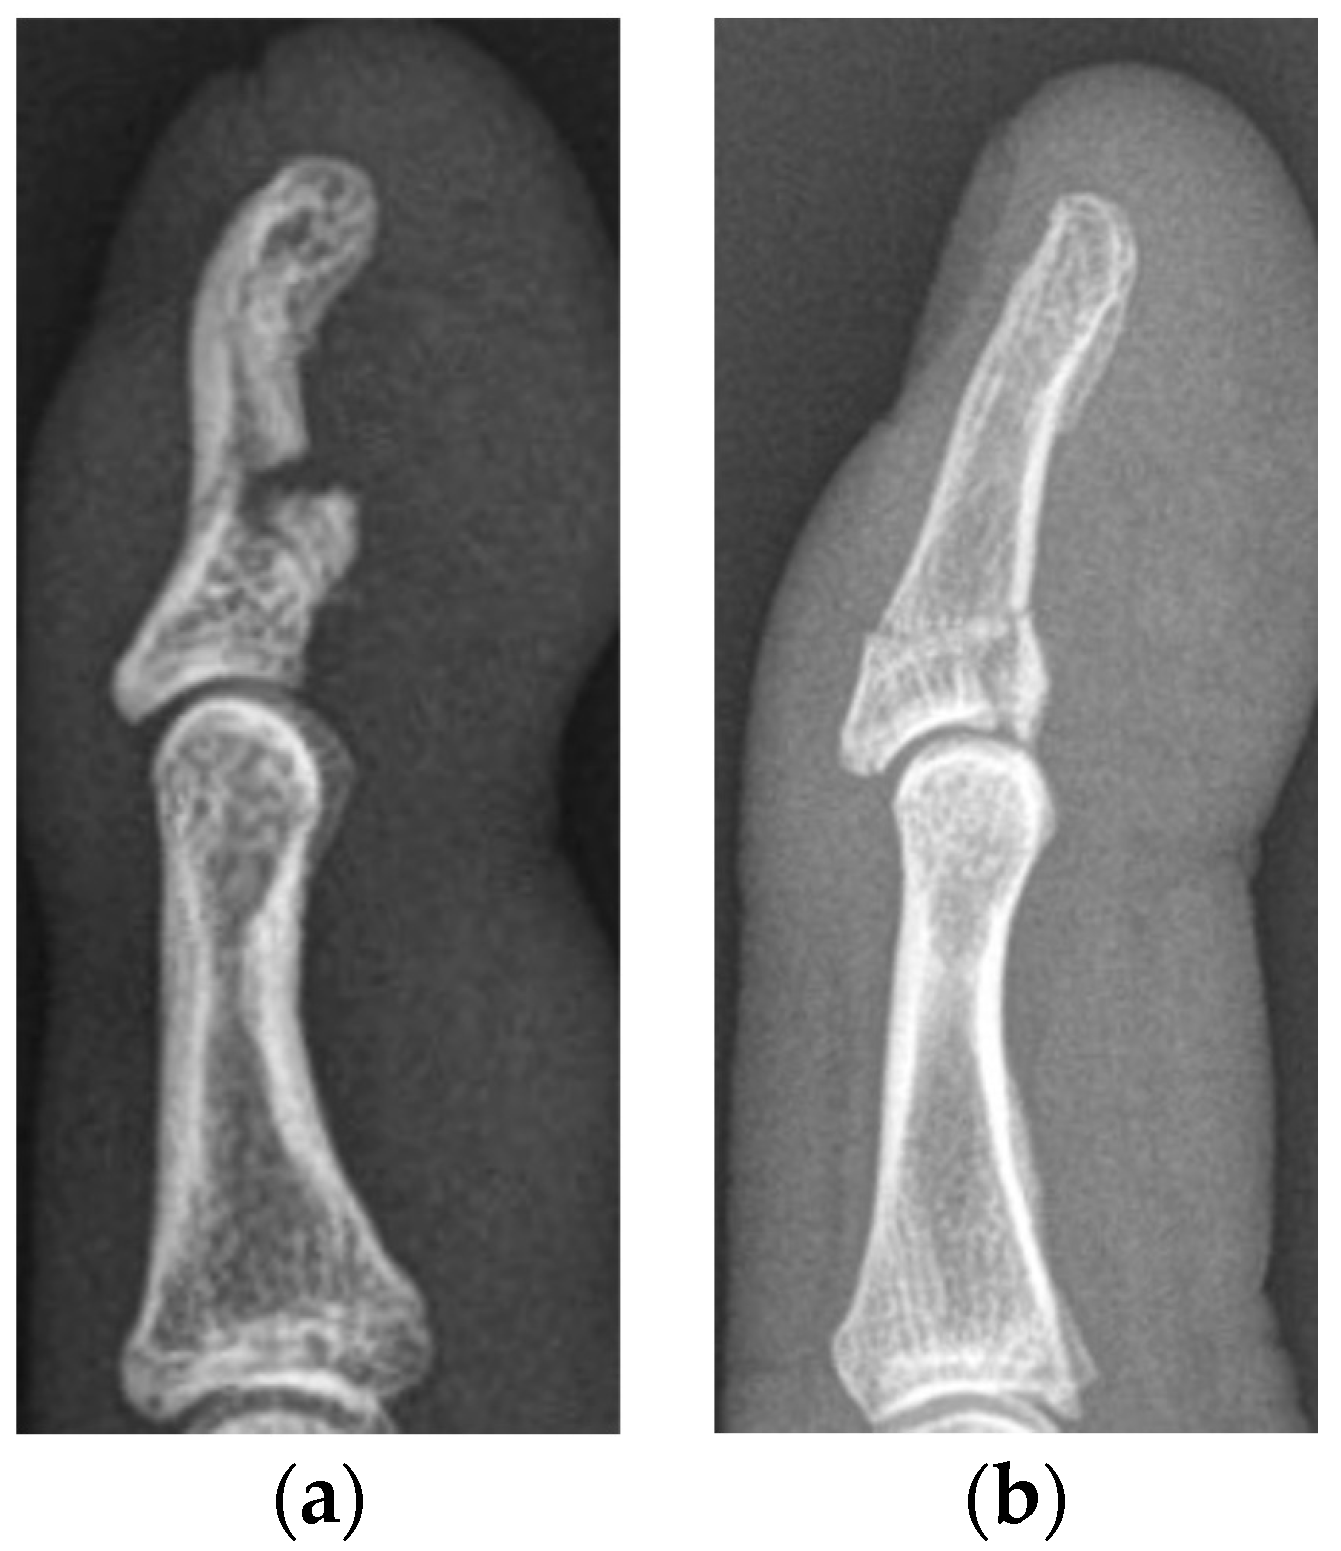

The median primary bony displacement in patients in the SD subgroup was 0.9 mm (0.6–3.0 mm). Significant retraction (level of PIP joint) of the FDP tendon was observed in every patient. The functional outcome in cases who subsequently underwent surgery was poor in one patient and fair in another. One patient who presented at our department was in clinical care at another trauma center. He had already undergone surgery; however, he showed signs of pseudarthrosis when he presented at our clinic and had already received an appointment for revision surgery. He consulted our department only once; further patient history and functional outcome were not recorded. Surgery was performed using Bunnell pull-out sutures and K-wires in all patients (Figure 3).

Figure 3. Lateral radiographs of a type Va jersey finger, with significant retraction of the FDP tendon together with a bony avulsion fragment (a). The same patient after surgical refixation using a K-wire and a Bunnell pull-out suture as proposed by Al-Quattan et al. [6] (b). Lateral radiographs after implant removal 6 weeks after surgery (c). The functional outcome of this patient was classified as fair.